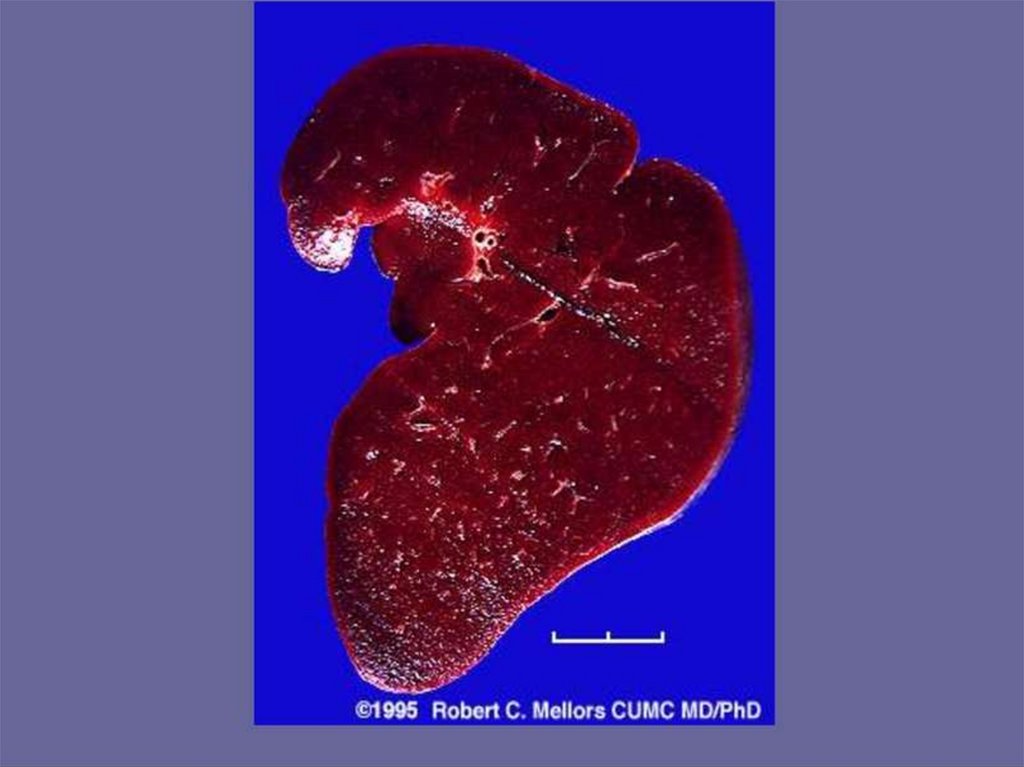

Внешний вид печени:

Увеличена, дряблая,

желто-коричневого

цвета. При разрезе на

лезвии ножа и

поверхности виден

налет жира.